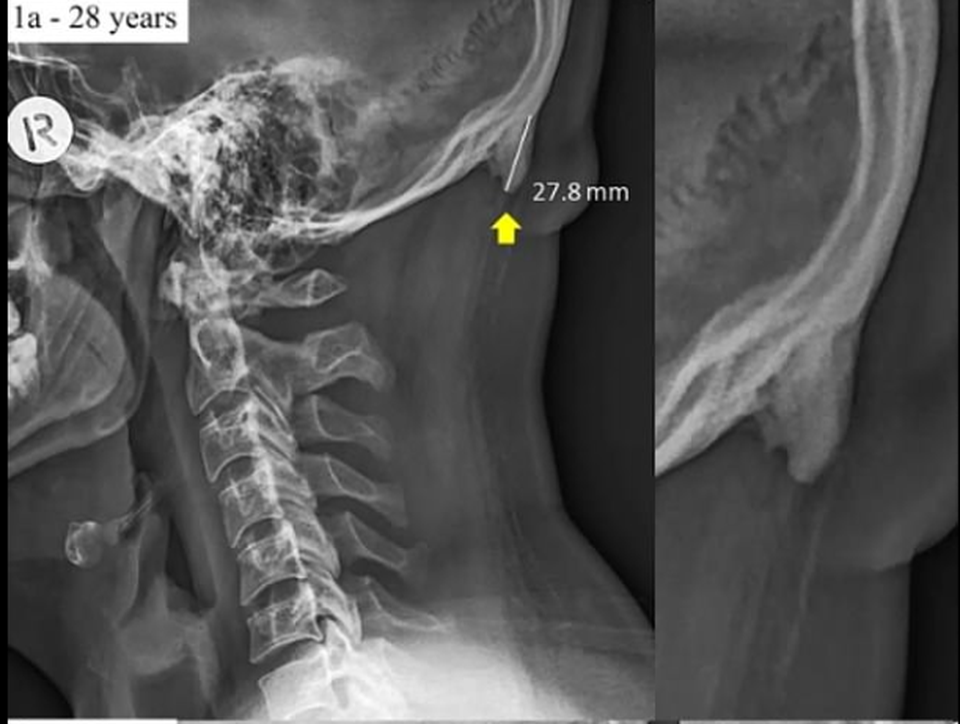

Như chúng ta đã biết, cơ thể con người vốn tồn tại cơ chế để tự thích nghi với điều kiện xung quanh. Theo cơ sở này, một tấm hình X-quang được giới thiệu bởi các nhà nghiên cứu tại Úc đã cho thấy nếu chúng ta liên tục sử dụng điện thoại, nghĩ về điện thoại của mình, hộp sọ có thể sẽ phát triển một phần xương cụt ở sau gáy, trông giống như một "cái đuôi".

Hiện tượng này có tên khoa học là lồi cầu chẩm ngoài (EOP), ghi nhận sự tăng trưởng của một phần xương lồi nằm ở đáy hộp sọ, đặc biệt là đối với những người trẻ tuổi.

Phần xương lồi ra của một người 28 tuổi.

Theo các nhà nghiên cứu, "cái đuôi" sinh ra bởi cách chúng ta nhìn xuống điện thoại và màn hình máy tính xách tay mỗi ngày. "Sự thay đổi cấu trúc não bộ có thể hình thành do sự căng thẳng, ức chế, khiến một vài bộ phận của cơ thể mà chúng ta thường sử dụng đã phát sinh thêm", tiến sĩ Shahar cho biết sau khi chụp X-quang hơn 1.000 hộp sọ của những người trong độ tuổi từ 18 đến 86.